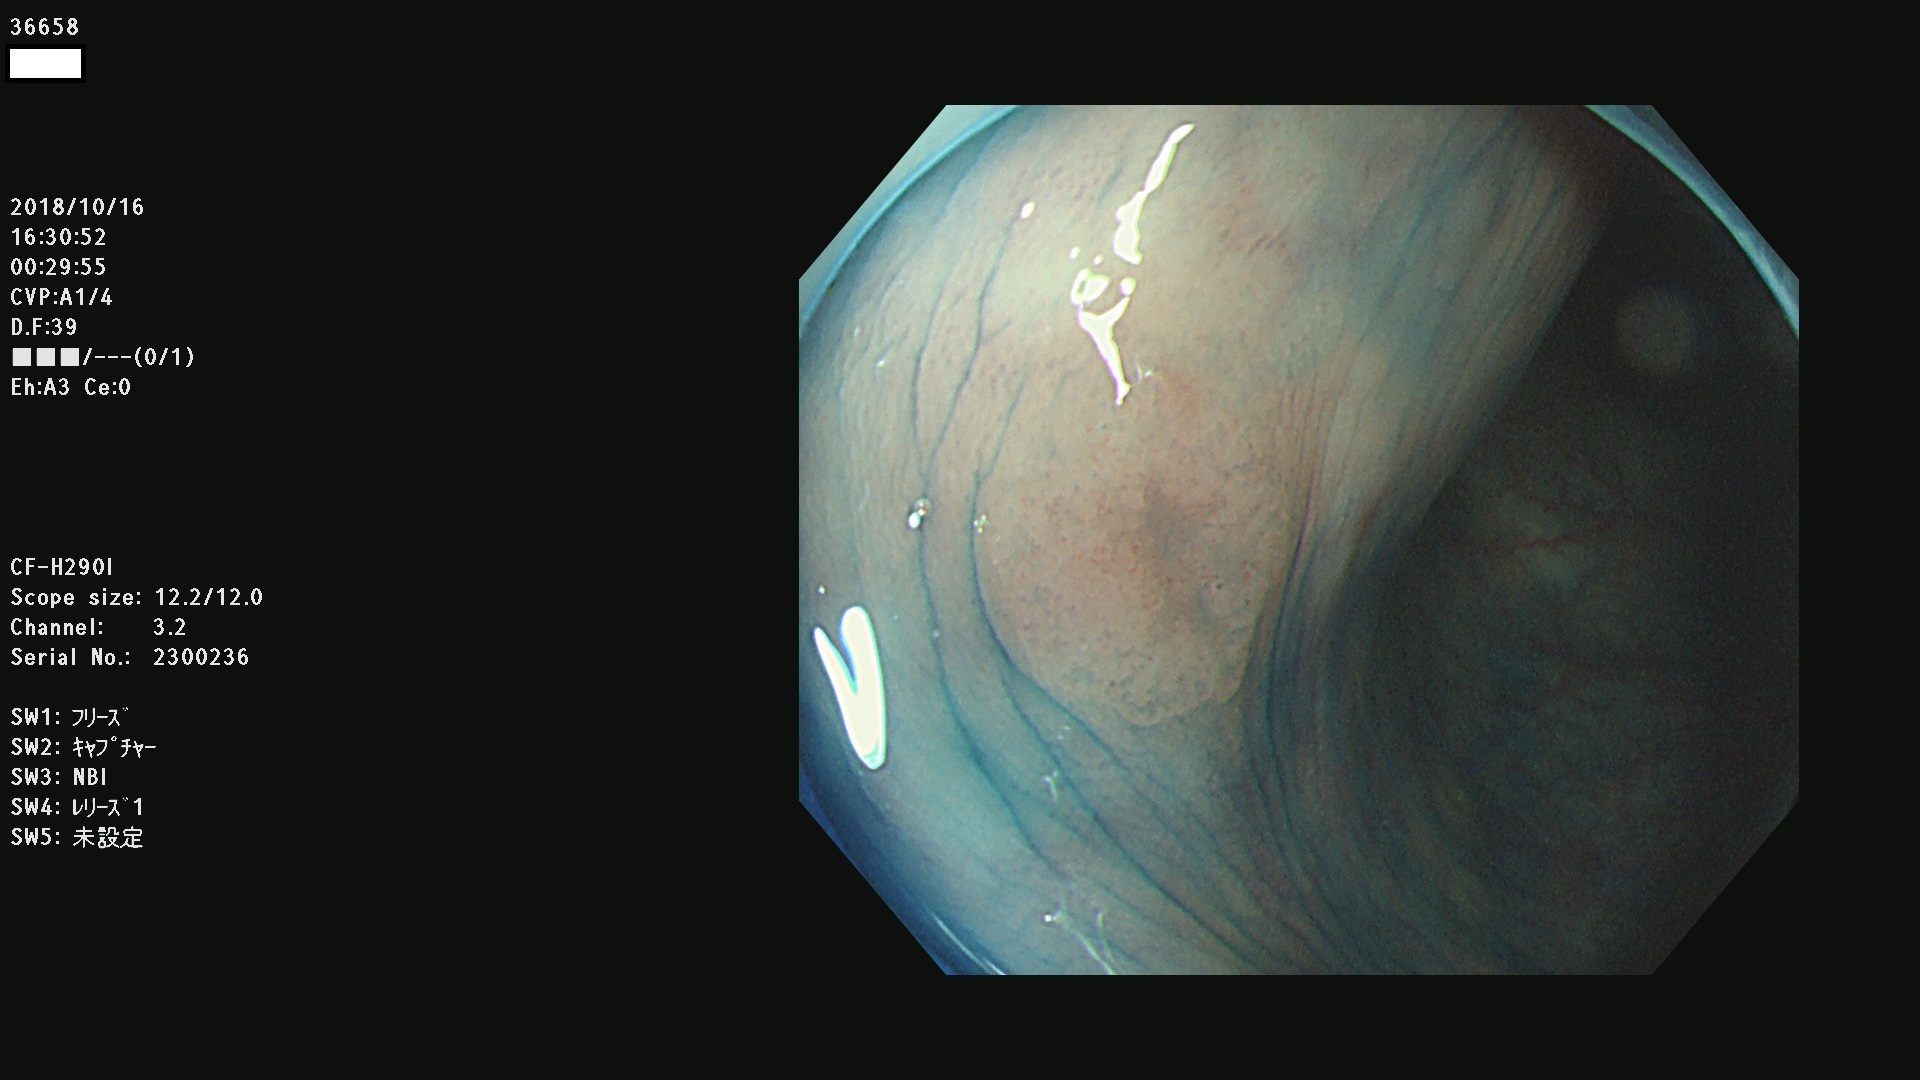

36600 36601 36603 36605 36606 36608 36609 36610 36611 36612 36613 36615 36617 36620 36621 36624 36625 36626 36627 36628 36629 36631(SSAPのみ) 36632 36633 36634 36636(SSAPのみ) 36637(SSAPのみ) 36639 36640 36642 36643 36644 36646 36647 36648 36649(SSAPのみ) 36650(SSAPのみ) 36652 36653 36654 36655(SSAPのみ) 36656 36657 36658 36659 36660 36661(SSAPのみ) 36665 36668 36669 36672 36673 36676 36677 36678 36679 36681 36682 36683 36684 36685 36687(SSAPのみ) 36691 36692 36693 36694 36695 36696 36697 36699(SSAPのみ)

発見困難で危険性の高い平坦型病変(上記100名より抽出)